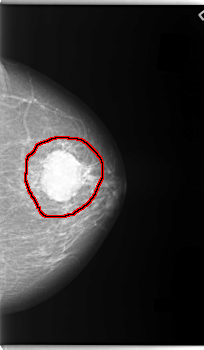

C_0088_1.RIGHT_MLO

FILE: C_0088_1.LEFT_MLO.OVERLAY

TOTAL_ABNORMALITIES 1

ABNORMALITY 1

LESION_TYPE MASS SHAPE OVAL MARGINS MICROLOBULATED

ASSESSMENT 5

SUBTLETY 5

PATHOLOGY MALIGNANT

TOTAL_OUTLINES 1

BOUNDARY